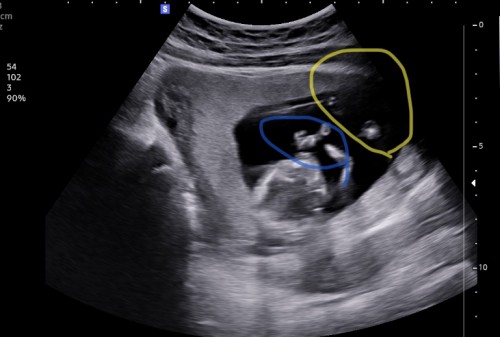

ในวงกลมสีเหลืองใช่เท้าน้องไหมคะ

13w คลิปซาวส่วนมากเห็นแต่แขน ไม่ค่อยเห็นช่วงขาหรือแม่ดูไม่ออกเองเลยจิตตกนิดนึง 😅 #ท้องแรกคะ

เหมือนเห็นตัวเองตอนท้องเลยค่ะ 😂 จิตตก ซาวด์ตอน 12 วีคแล้วคุณหมอไม่พูดถึงแขนขา จริงๆ น้องมีค่ะ อันเล็กๆ กำลังค่อยๆสร้างรูปร่างตัวเอง แม่ทำใจให้สบายน๊าาา บำรุงๆๆๆ ไปเรื่อย เดี๋ยวก็เห็นเต็มๆ เองค่ะ ถ้าไม่มี หมอต้องแจ้งแล้วค่ะ 🤭 ปล. บ้านนี้เคยผ่านความวิตก กังวล ตลอดการตั้งครรภ์มาแล้ว ตอนนี้คลอด 6 เดือนแล้วค่ะ